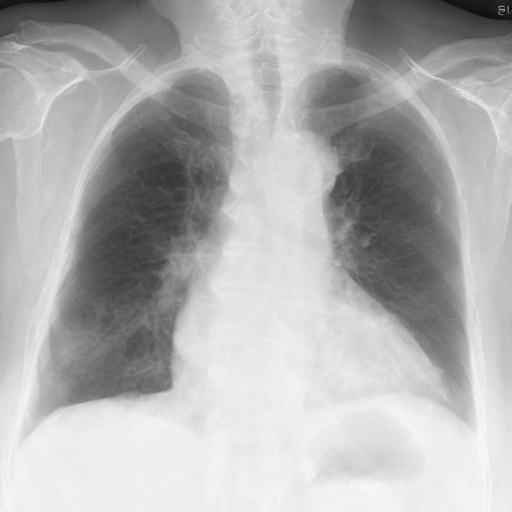

Let's load an example image of a patient with influenza.

For this example, we will remove the visual appearance of influence from the lungs, while preventing changes from happening to the rest of the image. To do this, we create a mask of the lung regions and use this as the edit_mask which defines the region we wish the editing prompt to be applied to. Since we want the rest of the image to remain unchanged, we use the inverse as the keep_mask which defines the region where edits are discouraged from taking place.